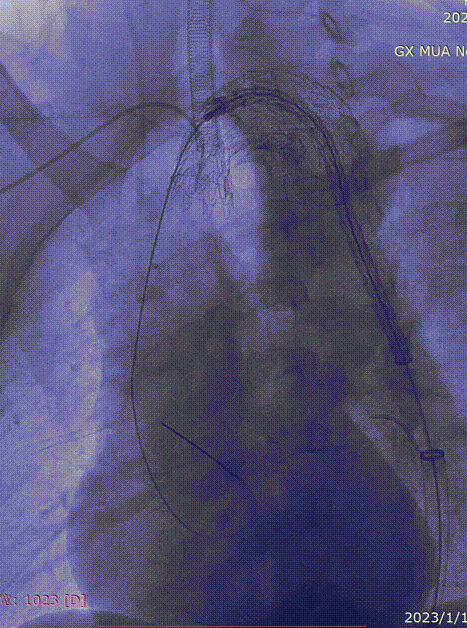

双导丝置入长鞘过弓

第一导丝用于平滑弓形角度,并稳定血管形态,第二导丝保持长鞘的前进方向与前者同轴。

即使有双导丝加持,长鞘在过弓的时候还是会遇到阻力,此时不要蛮力推进,可以轻微抖动回撤导丝,卸除一部分应力再尝试推进,切勿追求一步到位。

gore医疗怎么样「胸有乾坤」化险为夷,通险畅机——GORE® TAG® 胸主动脉覆膜支架治疗累及异形弓部动脉瘤_https://www.jmylbn.com_新闻资讯_第15张

单导丝塑形

双导丝导引弓部成型

引导鞘过弓

推送主体于目标锚定区更前端定位造影

支架输送系统塑型至弓部导丝支撑完成支架输送前置于LCCA前,将引导鞘退至降主。